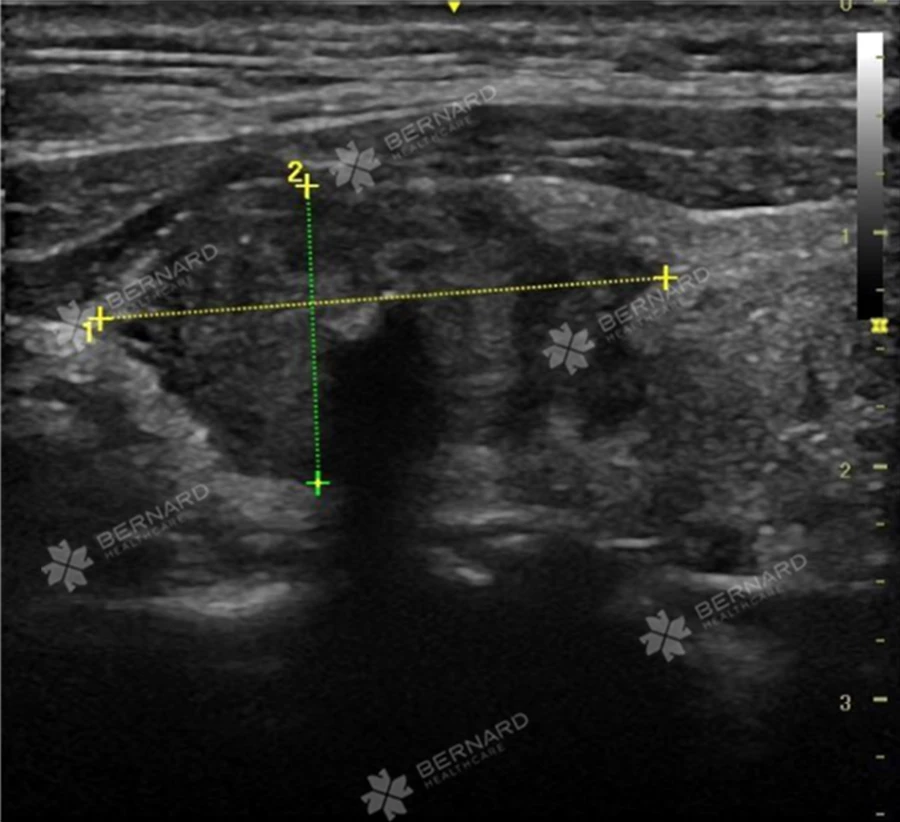

Khách hàng nam 37 tuổi, tiền căn khỏe mạnh, không có triệu chứng bất thường, đến Bernard Healthcare khám sức khỏe tổng quát. Từ kết quả siêu âm, bác sĩ chẩn đoán hình ảnh phát hiện nhân ở 2 thùy tuyến giáp.

Một nhân giáp thùy phải với kích thước #24x13 mm, TIRADS 5, bên trong có vôi hóa thô và vi vôi hóa, bờ không đều, nghi ngờ xâm lấn vỏ bao trước. Nhân giáp còn lại tại vị trí eo giáp với kích thước nhỏ #2x1.5 mm, TIRADS 4.